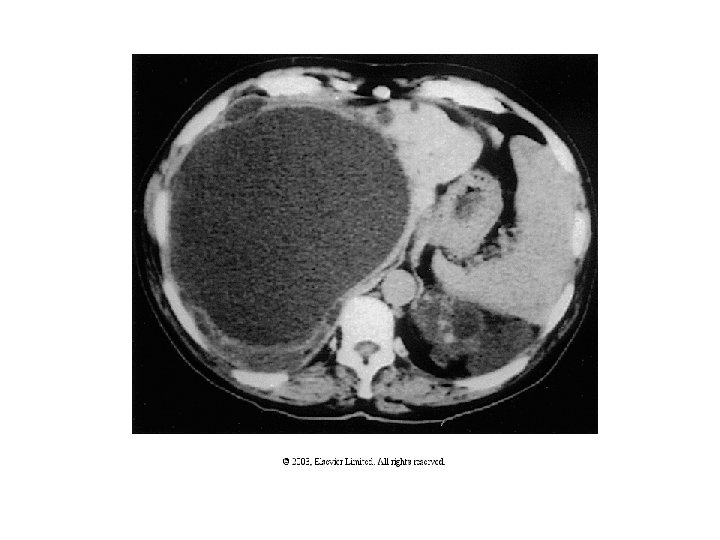

Rene policistico autosomico dominante dell’adulto (ADPKD, Autosomic Dominant Polycistic Kidney Disease) • • • Manifestazioni intorno alla 3°-4° decade di vita Non familiare fino al 25% dei casi Bilaterale Reni aumentati di volume, ma di aspetto “renale” Cisti distrib. omogeneamente tra corticale e midollare Originano da qualsiasi segmento nefronico Parenchima renale interposto non displasico Cisti epatiche (30% dei casi) Cisti pancreatiche (10% dei casi) Cisti tiroide, ovaio, endometrio, vescic. seminali, epididimo, etc. Anomalie cardiovascolari (18% dei casi) (Prolasso mitrale, Aneurismi aortici, etc) • Aneurismi arterie cerebrali (10 -22%) • Diverticolosi intestinale, ernia iatale, ernie addominali, diastasi dei retti

ADPKD: Manifestazioni • • Dolore addominale – Pielonefrite/infez. cisti – Nefrolitiasi (spesso uratica) – Emorragie cistiche – Diverticolite – Aneurisma addominale aortico – Nefromegalia Macro- microematuria (per rottura delle cisti) Ipertensione (50 -70% dei casi) Insufficienza renale cronica dalla 4° decade (>6° decade ca. 50% dei casi) Massa addominale Nefrolitiasi Eritrocitosi ADPKD tp 1 vs tp 2: 85 -90% dei casi vs. 10 -15%. Tp 2 comparsa più tardiva e più lenta evoluzione.

ADPKD: Diagnosi – Criteri primari • Numerose cisti omog. distrib. tra cortic. e midoll. • Reni grandi • Familiarità – Criteri secondari • • Fegato policistico Aneurismi arteriosi cerebrali Cisti pancreatiche Insuff. renale